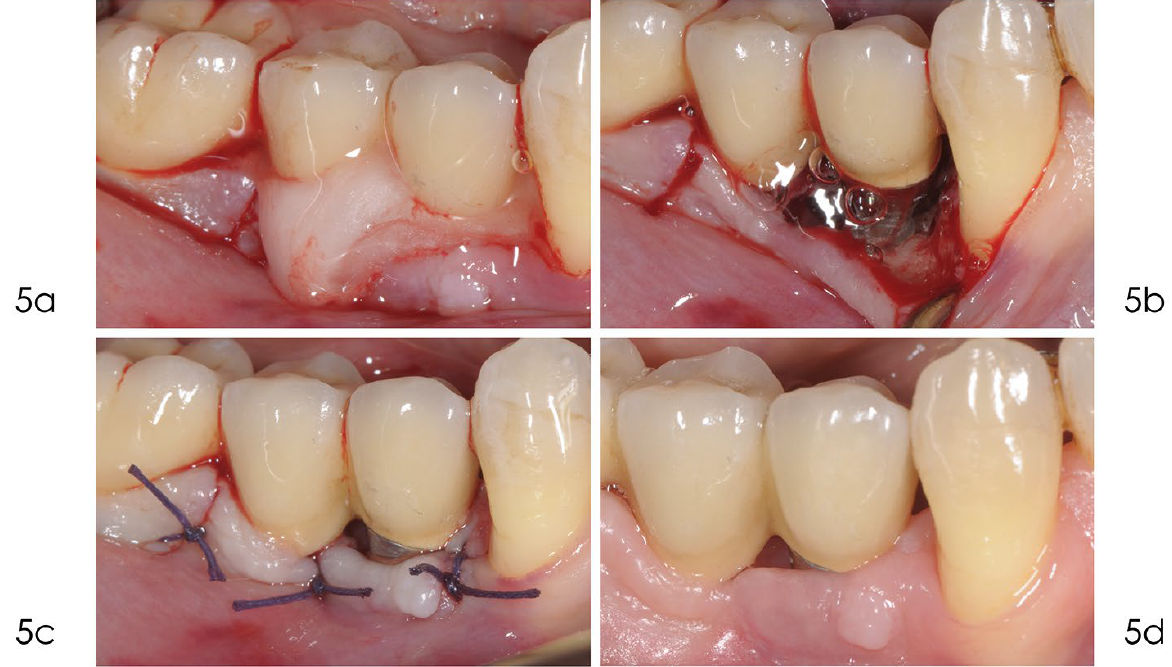

Фото 4. Обработка с доступом через лоскут

a) Рентгенограмма, выполненная через год после установки протеза, показывает оптимальный уровень кости вокруг имплантата. b) Кровоточивость при лёгком зондировании и глубина кармана 6 мм через пять лет после установки имплантата. c) Рентгенограмма, выполненная в декабре 2014 года, показывает краевую убыль кости в области имплантата 4.4. d) При отслаивании полнослойного лоскута выявлена убыль кости на уровне второго витка. Из-за тонкого костного гребня без внутриостного компонента было принято решение отказаться от реконструктивного подхода в пользу открытой инструментальной обработки

Фото 5. a) После удаления грануляционной ткани поверхность имплантата была обработана 24% ЭДТА в течение двух минут. b) После промывания физиологическим раствором на поверхность нанесён гель хлоргексидина 1% на две минуты. c) Шов нитью Vicryl 4/0 обеспечивает оптимальное открытое (непогружённое) заживление. d) Заживление проходит без осложнений

Фото 6. a) Рентгенограмма, выполненная в сентябре 2020 года, через десять лет после установки имплантата, показывает стабильный костный дефект. b) Клиническое изображение, сделанное в сентябре 2020 года, демонстрирует отсутствие воспаления в мягких тканях вокруг имплантата. c) Рентгенограмма, выполненная в январе 2024 года, подтверждает отсутствие дальнейшей потери кости дистально и небольшое улучшение с мезиальной стороны. d) Клиническое изображение, сделанное в январе 2024 года, показывает минимальную рецессию мягких тканей через 14 лет после установки имплантата. Зондирование выявляет стабильную, хотя и не идеальную, глубину пародонтального кармана